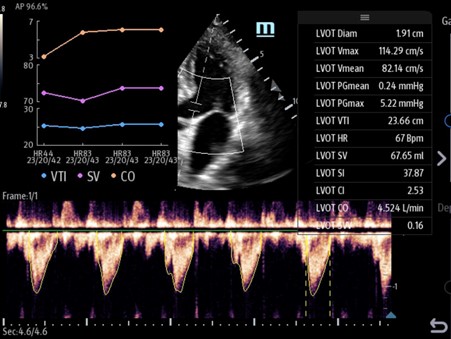

Pulsed wave Doppler

Pulsed Wave Doppler is used primarily in echocardiography but has some applications within abdominal imaging. As the name suggests, Pulsed Wave Doppler uses rapid pulses to measure flow. When activating Pulsed Wave Doppler, you first position the sample volume over the region of interest. This is shown as two horizontal lines on a vertical line.

Pulsed Wave Doppler is region-specific, meaning velocity measurements are taken precisely from the location where the Sample Volume (SV) is placed. However, because it must wait for each pulse to return before sending the next, and due to the speed of sound in tissue, it is limited by a maximum measurable velocity known as the Nyquist limit.

To overcome this limitation, some systems offer a High Pulse Repetition Frequency (HPRF) mode, which sends new pulses before previous echoes have returned. This increases the velocity range but sacrifices exact location accuracy, as multiple sample volumes may appear—indicating that the measured velocity could originate from any of those regions.